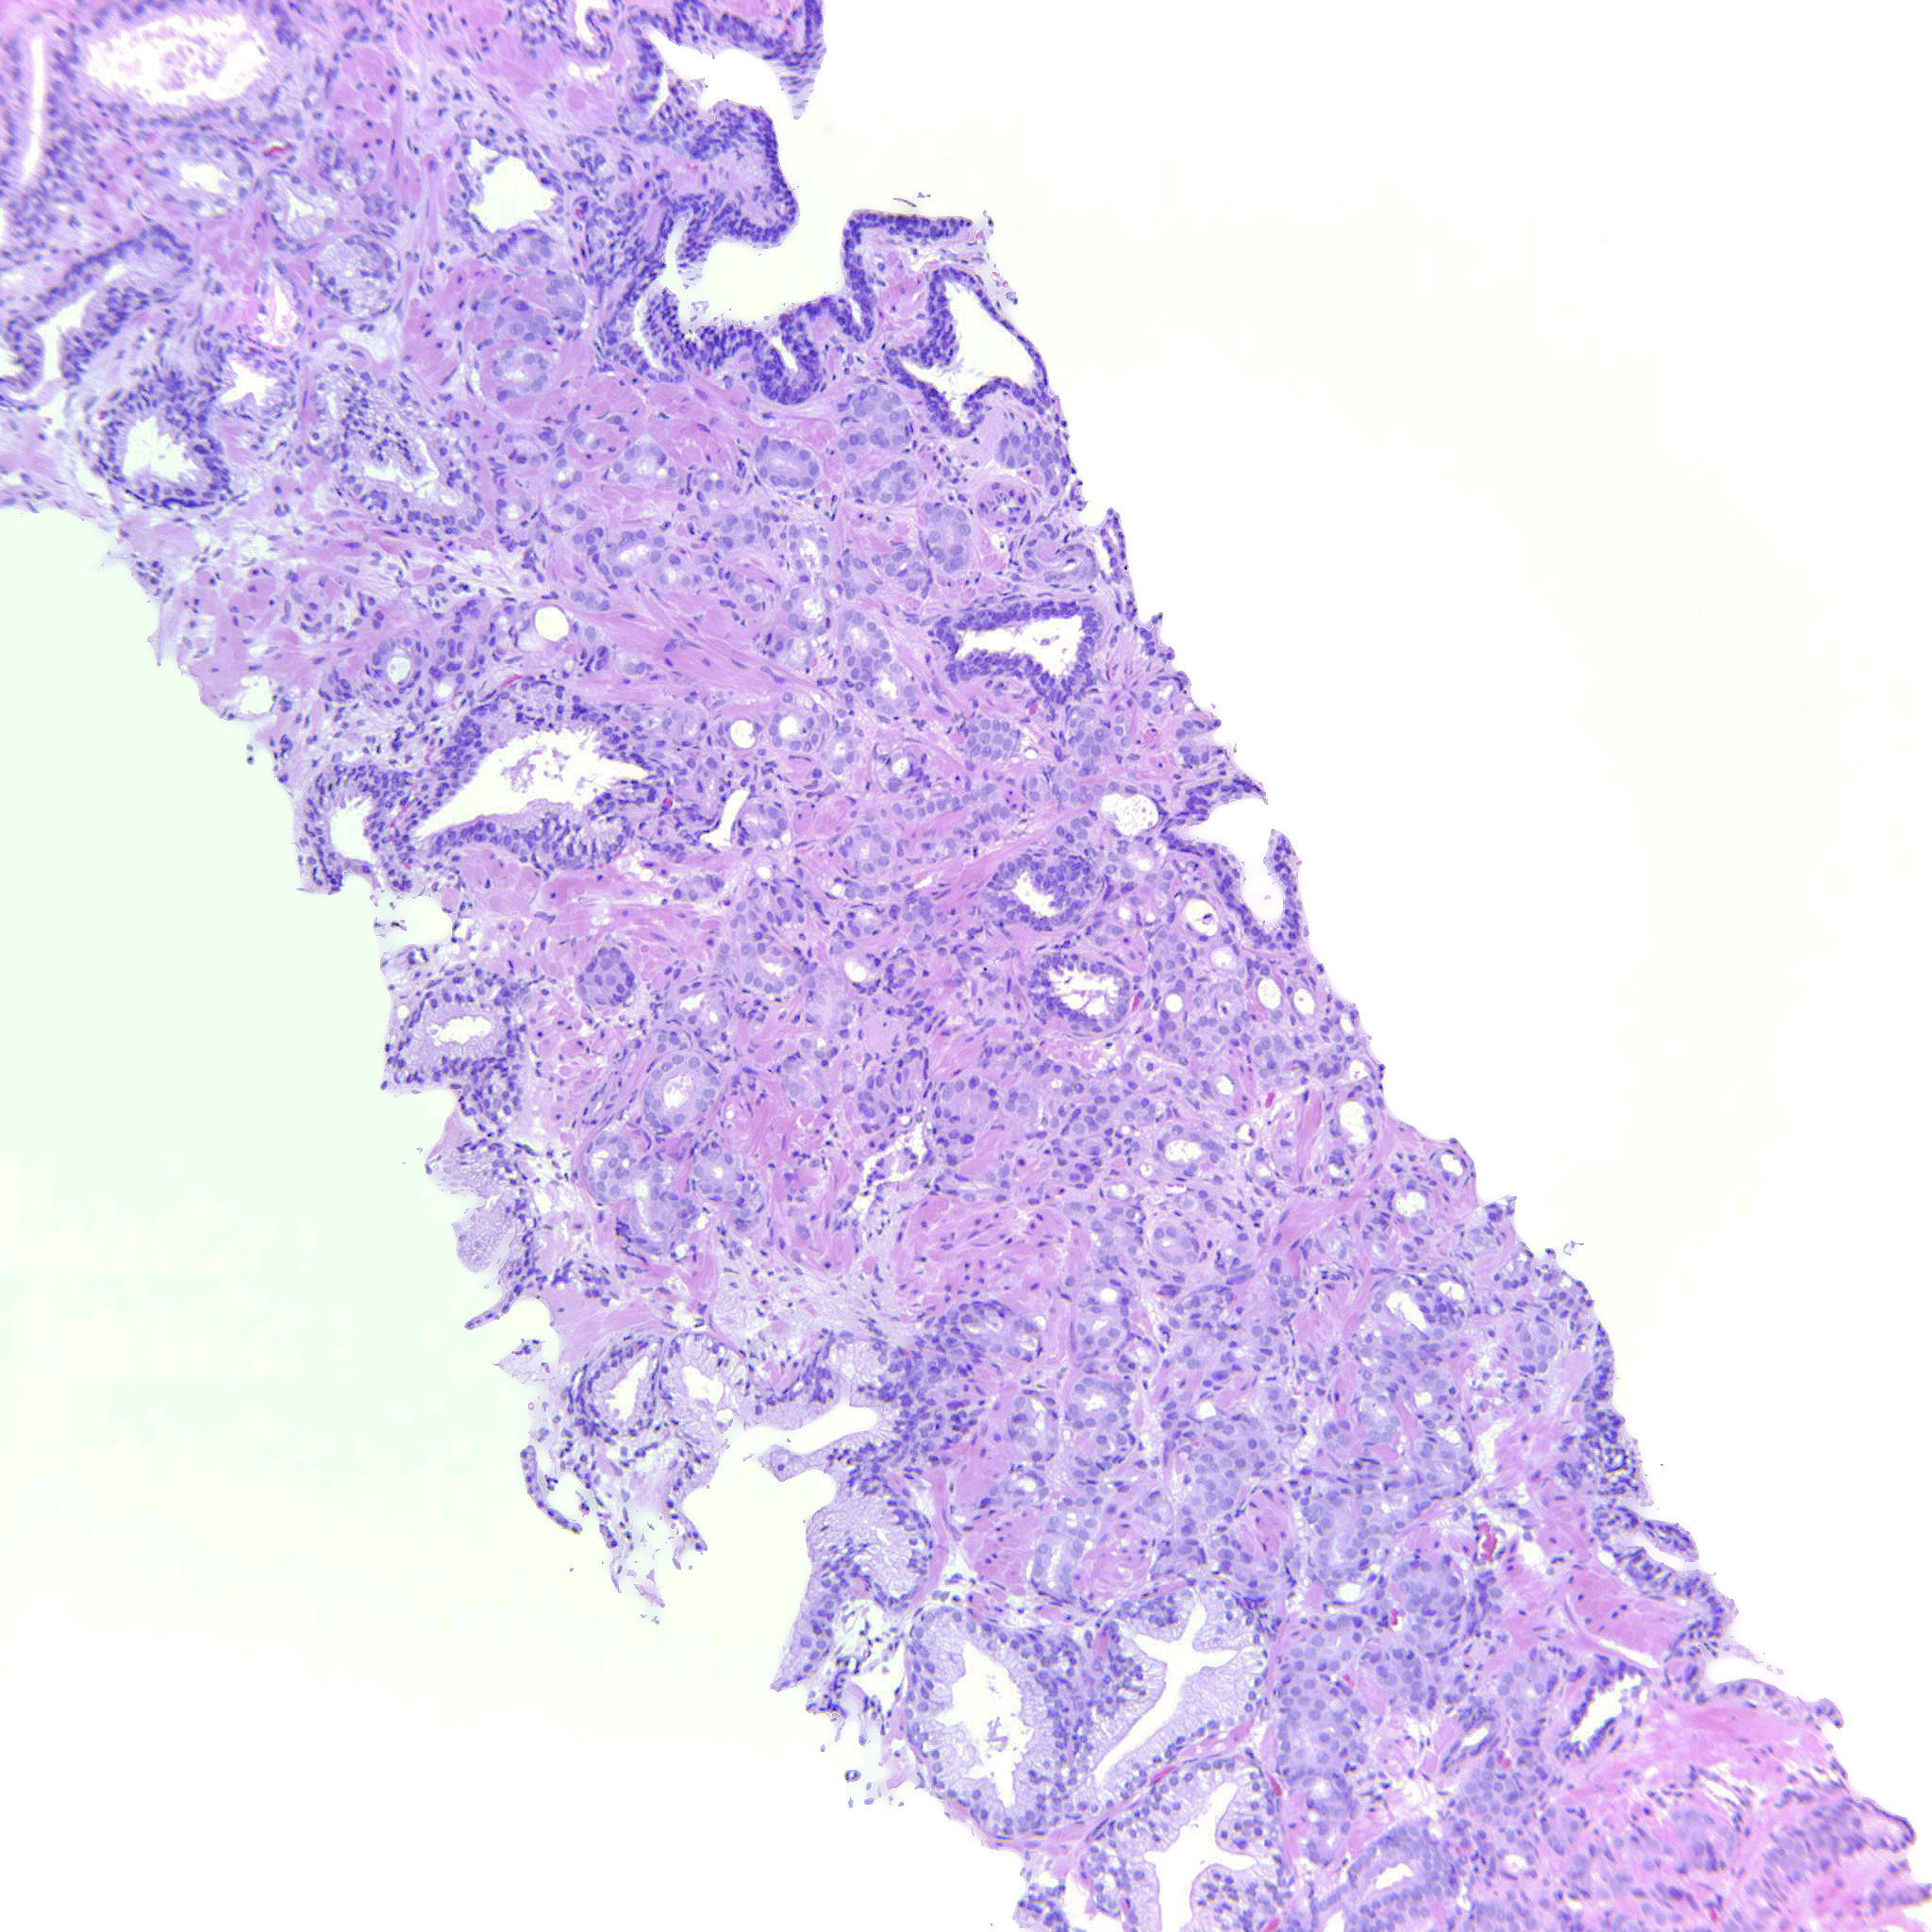

Prostate cancer grading

Case ID: 487